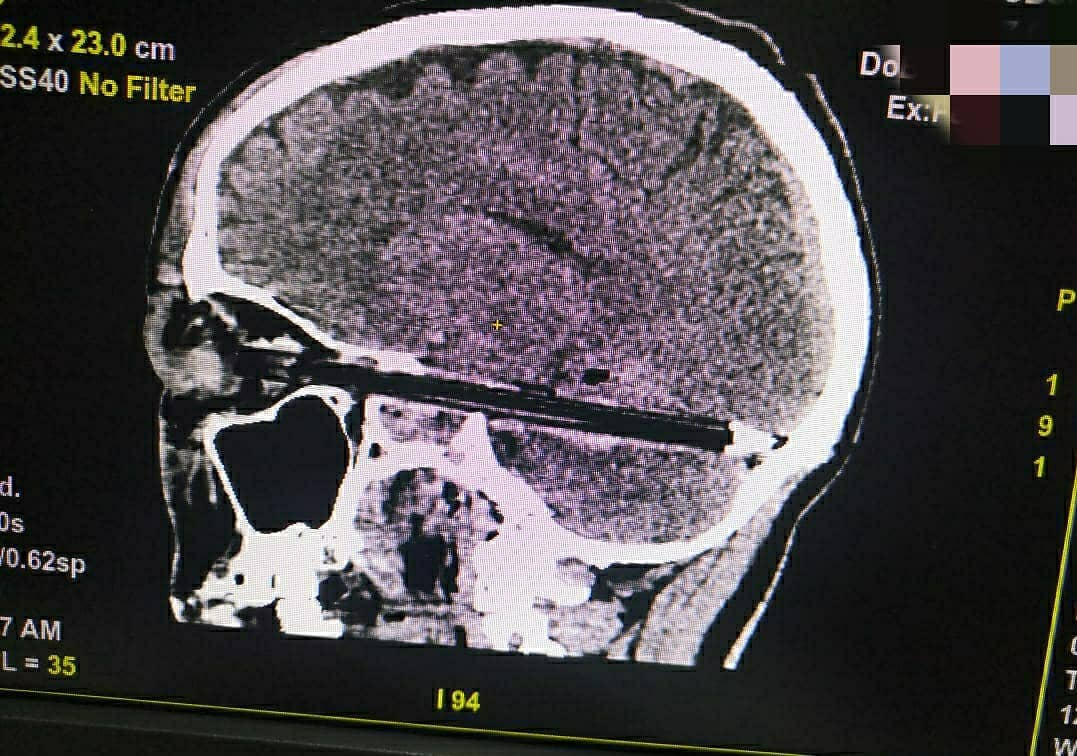

Мужчину доставили в больницу через день, вечером 6 февраля, и тогда же прооперировали. Ручка, как говорили представители больницы скорой медицинской помощи, через глаз прошла в мозг на весь диаметр черепа «в миллиметре от жизненно важных сосудов и ствола головного мозга». Он умер 9 февраля в реанимации.